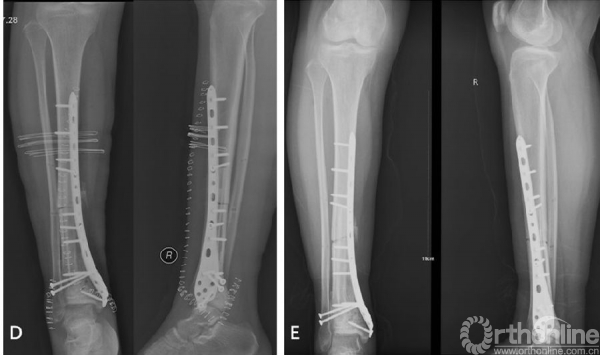

图2女性/16岁,右胫骨下端骨肉瘤。A术前X光片,右胫骨下端骨肉瘤,后方软组织包块影伴肿瘤性成骨。B化疗后MRI显示胫骨下端异常信号影。C术中完整切除胫骨远端肿瘤后刮除髓腔内肿瘤、65℃ 20%高渗盐水灭活30分钟后原位回植、对侧自体腓骨置于髓腔中心、钢板内固定、LARS韧带重建内踝软组织、下胫腓关节融合。D术后即刻X光片。E术后6个月X光片显示截骨面已模糊。F术后踝关节功能良好,7个月后无需支具辅助可正常行走。